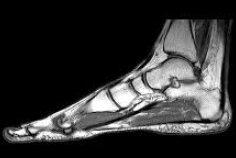

A physical examination is usually done, but it may be difficult to carry out due to pain. Diagnostic measures may include: blood and urine tests; neurological and muscle strength examinations; magnetic resonance imaging (MRI); and computed tomography (CT) scan. Muscle strength is tested and graded on a scale of 0 (none) to 5 (normal). A muscle enzyme test, creatine kinase (CK-MM), muscle biopsy, and electromyogram (EMG) may be done.